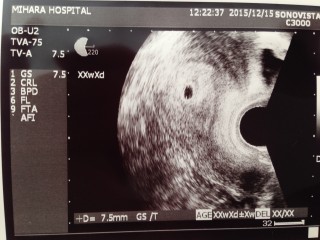

胎嚢は7.5mmでした! 結婚して2年2ヶ月なかなか授からず、年明けから不妊治療を開始しようかと話していた矢先のことでした。 2週間後に胎芽と心拍確認のためにまた病院に行きます。